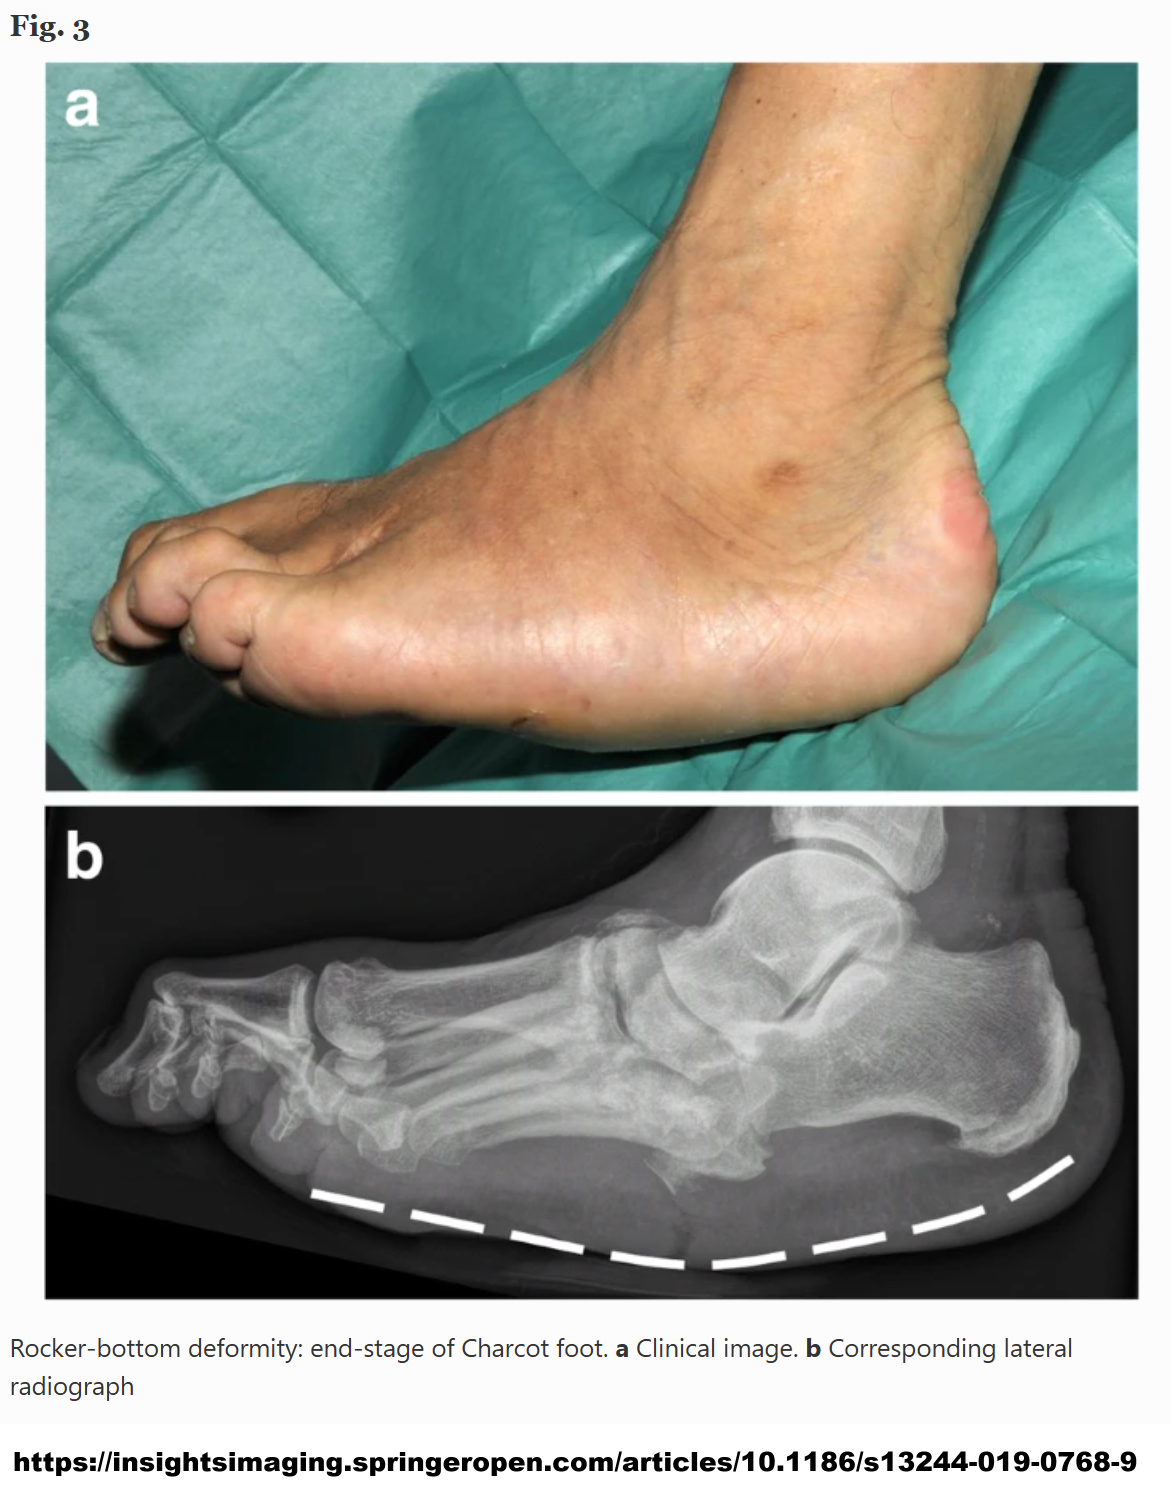

7. 물론 당뇨를 오래 앓고 신경병증이 악화되면 결국 교감신경과 운동신경도 손상됩니다. 뒤에서 다룰 저혈당무감지증이나 기립성 저혈압은 교감신경의 손상으로 촉발되는 증상으로 심각한 합병증 중 하나입니다. 운동신경이 손상되면 발 근육의 위축이나, 발 변형으로 이어지기도 합니다. 하지만 교감신경과 운동신경은 활성산소에 조금 더 견고한 구조여서 비교적 늦은 시기까지 기능이 유지되므로 진료실에서 흔히 마주치는 것은 아무래도 교감신경의 항진과 관련된 증상입니다.

CHARcot.png